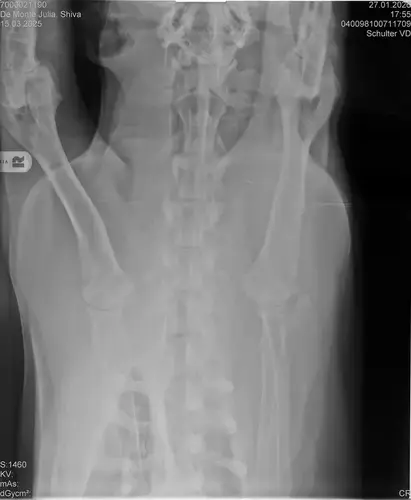

• Naja die Diagnose kommt von einem „Facharzt“, lt TA war ihrerseits alles i.O. Sie wollte noch sicher gehen und die Bilder zur weiteren Befundung einschicken und das kam dabei raus. Und der Therapievorschlag beläuft sich auf Ruhe, Ruhe und noch mehr Ruhe. Und einer Schmertherapie von Gabapentin 800mg 1/2 Tablette 2x tgl, Carprodyl 120mg 1 1/2 Tabletten 1x tgl und TamaCan CBD Tropfen 10-15 Tropfen 2x tgl. 1x in der Woche soll ich telefonisch Auskunft geben wie es Shiva geht. Das ganze mal für 14 Tage. Sie meinte noch sie hat viele Junghunde die ein Leben lang Schmerzmittel nehmem müssten. Die Röhrenknochenentzündung heilt in der Regel von selber der Rest gehört beobachtet… Ich weiß im Moment auch nocht so recht.. Er tut mir nur wahnsinnig leid mit sovielen Diagnosen und für mich war erstmal vorrangig ihn schmerzfrei zu bekommen. Das ist er inzwischen und versteht die Welt nicht mehr warum er nicht wie sonst spielen und arbeiten darf. Im Anhang noch Röntgenbilder falls sich jemand damit auskennt bzw Interesse hat..

Vielleicht würde es sich lohnen später nochmal ein DSH-spezifisches Röntgen bei einem Fachmann vom SV machen zu lassen um die Werte für HD und LÜV ganz konkret zu haben. Evtl. macht sich die Hüfte und der Rücken ja im Moment gar nicht bemerkbar und wenn Shiva nicht im Hochleistungssport eingesetzt wird, bekommt er vielleicht nie gravierende Probleme?

• Ich habe Lex seine Röntgenbilder auch noch mal von einem SV Spezialisten anschauen lassen, LÜW und noch was, der Züchter hat nur HD und ED vom SV begutachten lassen.

Wenn dieser Panostitis-schub rum ist, würde ich dem Rest nochmal nachgehen. Man kann bei Dr. Tellhelm ( SV Gutachter) ein privatgutachten in Auftrag geben, das kostet um die 100€. Da kriegst du halt ne konkrete Einstufung und nicht "verdacht auf" und "könnte hiermit ODER damit in Verbindung stehen", etc.

Ich denke aber, dass du für ein Gutachten von Tellhelm nochmal neu röntgen lassen musst, ich finde, dass das Bild der Hüfte (HD und LÜW wird da beurteilt) und die Draufsicht auf die Ellenbogen (nötig zur Beurteilung von ED) unterirdisch sind!